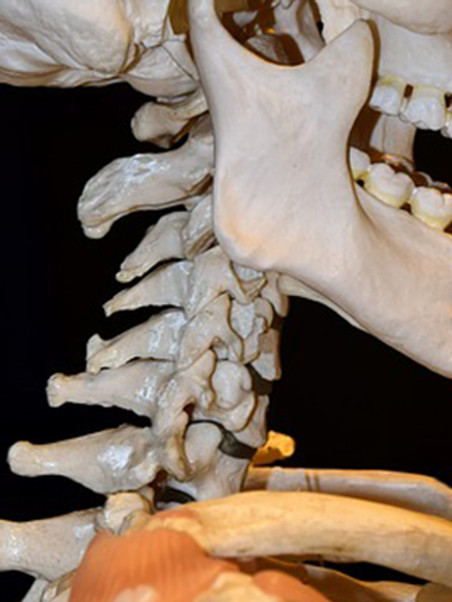

목 디스크란 경추 뼈와 뼈 사이의 추간판 ( 디스크 )이 탈출하였거나 파열돼 경추신경이 자극 또는 압박을 받아 경항부 ( 목 ), 경견부 ( 목과 어깨 ), 견배부 ( 어깨와 등 ), 상지 ( 팔 )에 통증 및 신경학적증상을 나타내는 질환 이고요. 경추는 운동성이 큰부위 이예요.

경추의 디스크는 난폭한 압력을 받으면 돌출하여 척수나 신경근을 억누르게 된다고 합니다. 대부분의 목 디스크는 난폭한 퇴행성 전환 향후에 발생하기 때문에 많은 환자들이 만성적인 경항통 ( 목의 통증 )에 대한 오래전력을 갖고 있다고 한다면가 대다수 이고요. 그럼 이제부터 적극적으로 목 디스크에 좋은 운동을 따져보도록 하겠습니다.